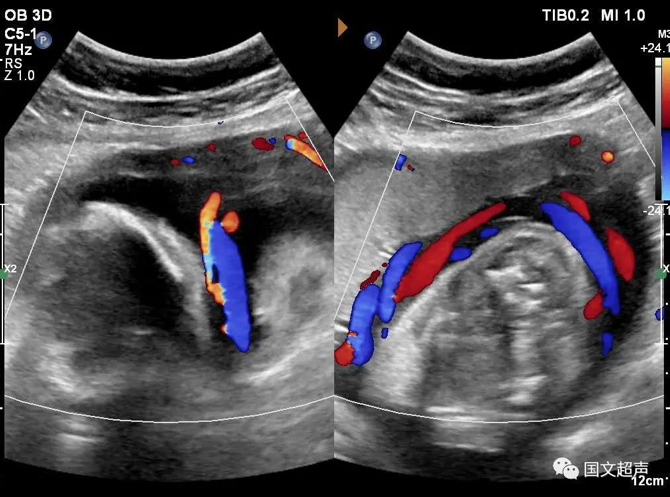

四.關于臍帶繞頸

臍帶有補償性伸展,纏繞松弛對胎兒影響不大,但如果纏繞過緊可影響胎兒血供,有造成胎心率改變、胎兒缺氧、窒息甚至胎死宮內的風險。

實際上影響胎兒預后的主要因素不在于繞頸的周數,而在于除去繞頸所剩的臍帶長度。如果孕媽媽只繞頸一周但臍帶相對過短,仍可造成不良結局。

臍帶繞頸的孩子很多,但發(fā)生不良結局的確占少數,所以不必過度擔心,只要每天的胎動正常,沒有突然的增多和減少,定期復查即可。